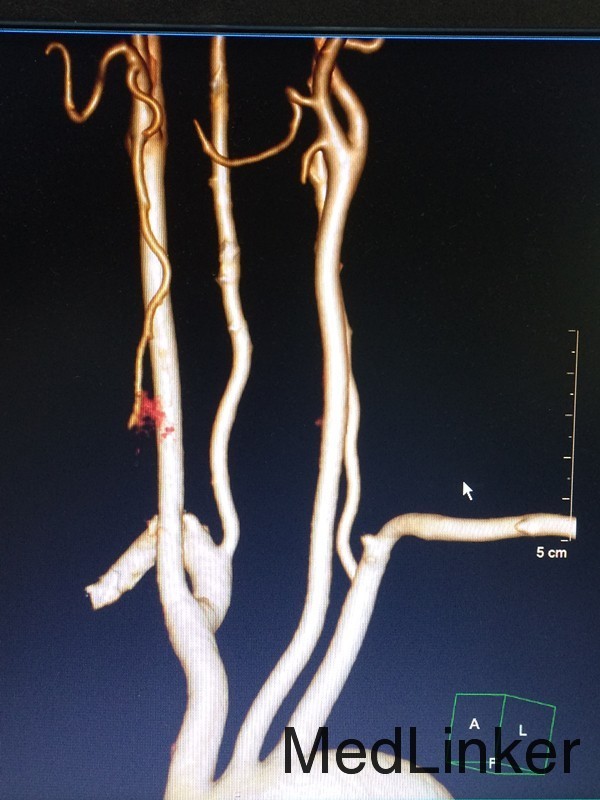

查体:左侧上肢2级,下肢2级,右侧肢体肌力正常 辅助检查:查头颅CTA提示:右侧额叶及岛叶(包括基底节)脑梗塞,轻度脑萎缩,CTA未见明显异常

随访:患者病情缓解出院 讨论:患者60岁男性,突发大面积脑梗塞,可能是由脑动脉主干阻塞所致,CT呈现大片状低密度阴影,多为脑叶或跨脑叶分布,脑组织损害范围较大,临床上除表现脑梗塞的一般症状外,还伴有意识障碍及颅内压增高。不排除为体循环的血栓掉落至大脑动脉引起。